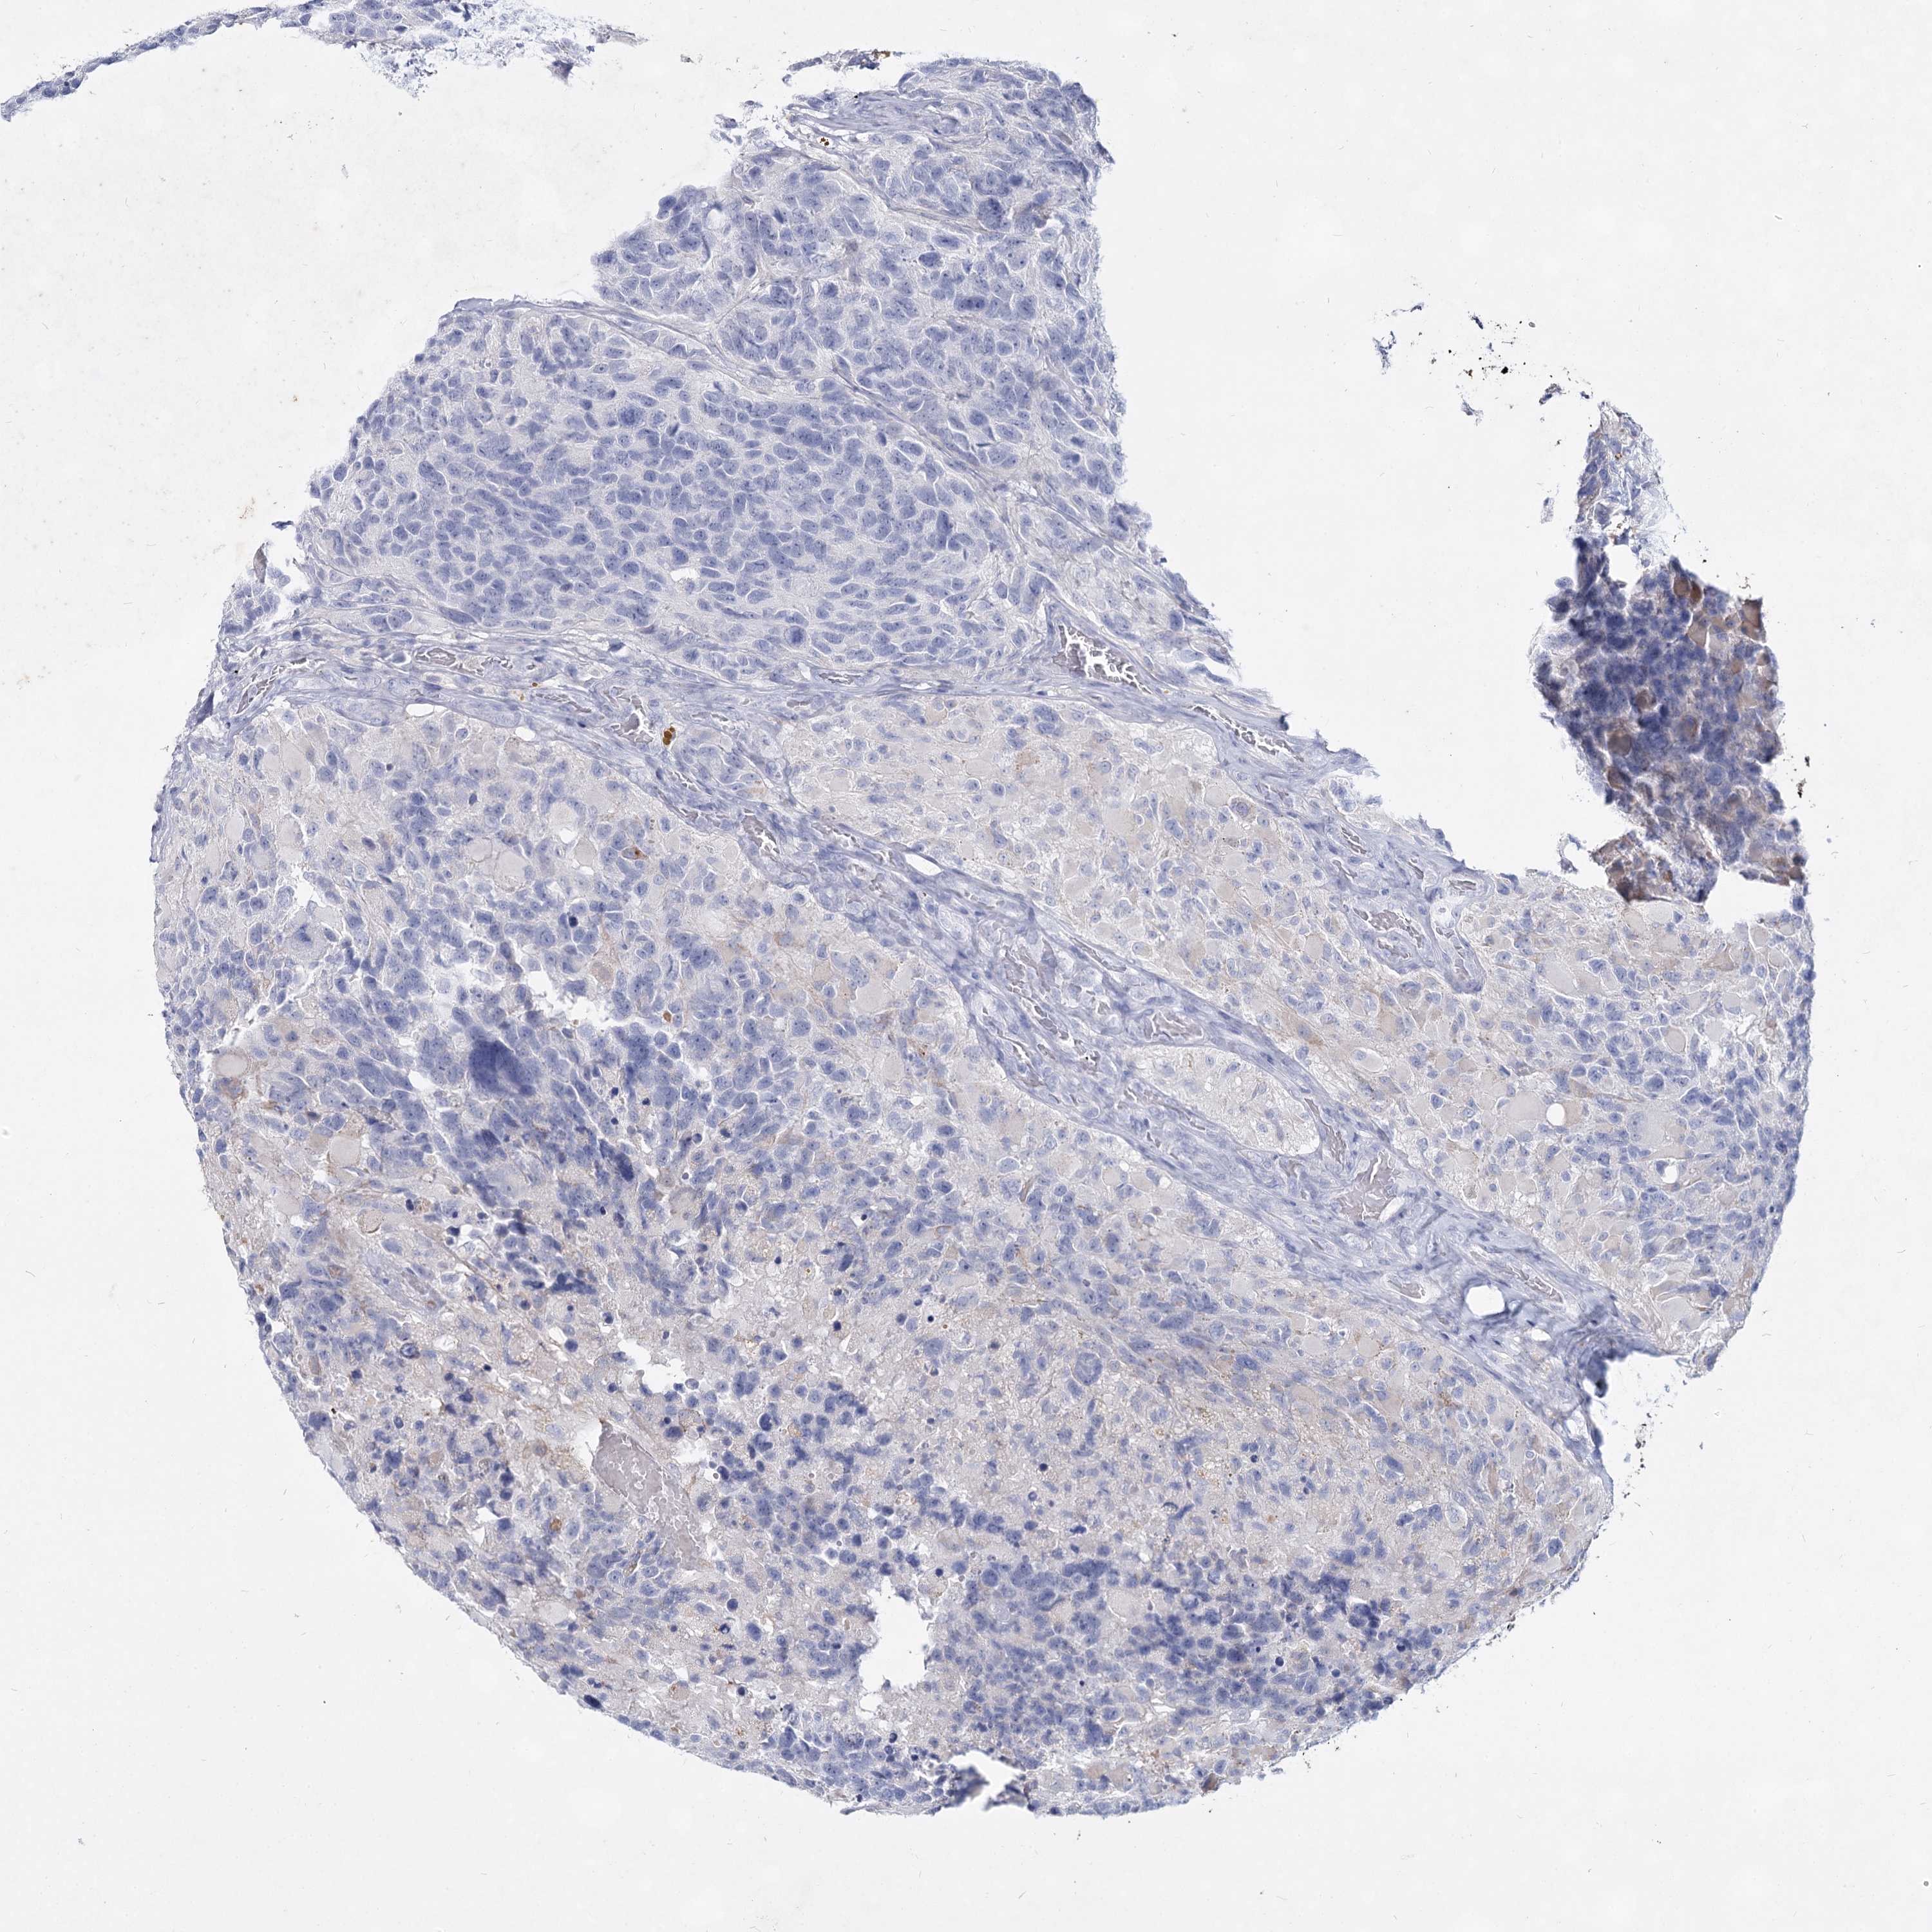

GLIOMA - Protein expressioni

A mouse-over function shows sample information and annotation data. Click on an image to view it in a full screen mode. Samples can be filtered based on level of antibody staining by selecting one or several of the following categories: high, medium, low and not detected. The assay and annotation is described here.

Note that samples used for immunohistochemistry by the Human Protein Atlas do not correspond to samples in the TCGA dataset.

Antibody stainingi

Antibody staining in the annotated cell types in the current human tissue is reported as not detected, low, medium, or high, based on conventional immunohistochemistry profiling in selected tissues. This score is based on the combination of the staining intensity and fraction of stained cells.

Each image is clickable and will lead to virtual microscopy that enables deeper exploration of all samples and also displays staining intensity scores, fraction scores and subcellular localization as well as patient and tissue information for each sample.

Antibody HPA038668

Antibody HPA038669

Staining

High

Medium

Low

Not detected

Intensity

Strong

Moderate

Weak

Negative

Quantity

>75%

75%-25%

<25%

None

Location

Nuclear

Cytoplasmic/membranous

Cytoplasmic/membranous,nuclear

Glioma, malignant, High grade

Glioma, malignant, Low grade

Glioblastoma, NOS